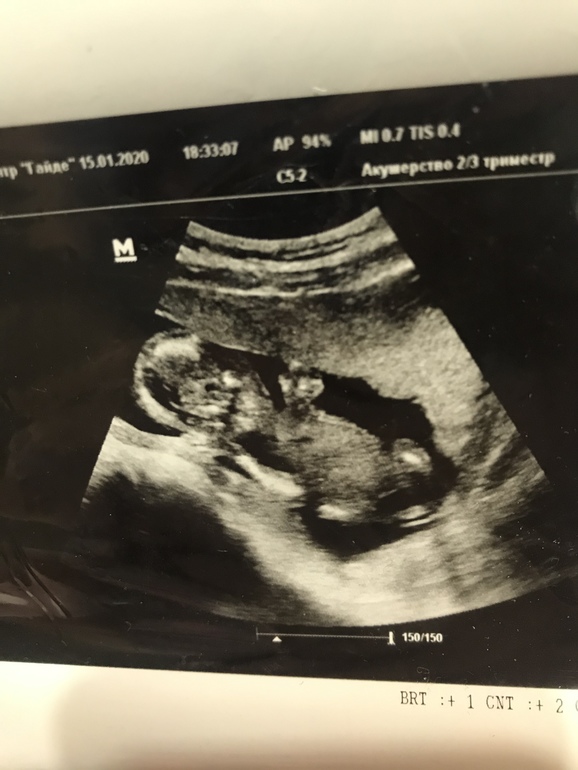

Пол малыша16+4 недель, сходила на платное УЗИ

Шейка 40 мм, плацента поднялась очень хорошо, зев закрыт 👌🏻

Малышка хороша 👍 12 см ростом, ручки и ножки длинненькие (ну, нам ещё на 1 скрининге сказали - будет модЭль😄). Врач сказала большие глазницы у крошки, в маму видно будет - глазастая 😉 Сердце 150 ударов. По всем параметрам - всё как по учебнику 🤞 и развиваемся срок в срок 🥰 Ну и нос, конечно, же в полном порядке 😂 Малышка показала нам пятюню, закрывала личико ручками, крутилась и вертелась ))